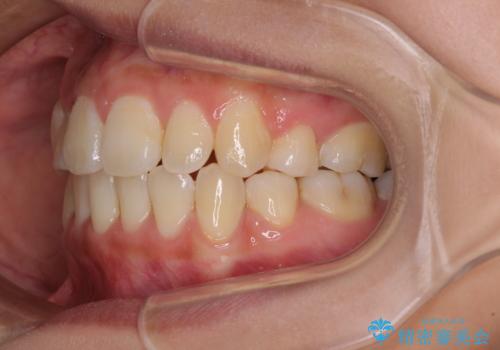

- 八重歯を気にして来院された患者様です。

上下ともに前突感と叢生が認められ、上顎の正中が著しく右側にずれていたため、上下左右第一小臼歯4本を抜歯し、ワイヤー矯正にて治療を行うこととしました。

移動量が多かったため、治療期間は通常より半年~1年ほど長くかかりましたが、上下の正中をほぼ同じ位置にまで移動させることができました。